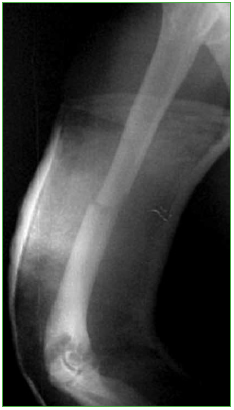

Mujer de 43 años, oficinista, con politraumatismos por un accidente automovilístico de alta energía: fractura subtrocantérica de fémur derecho, fractura del tercio medio del húmero derecho (Figura 1), fracturas de cúbito y radio distales derechos, y múltiples fracturas costales. Sin lesión nerviosa ni vascular. No tiene antecedentes familiares ni personales de relevancia.

Figura 1.

Radiografías de diáfisis del húmero derecho obtenidas el día del traumatismo. Se observa una fractura transversal.